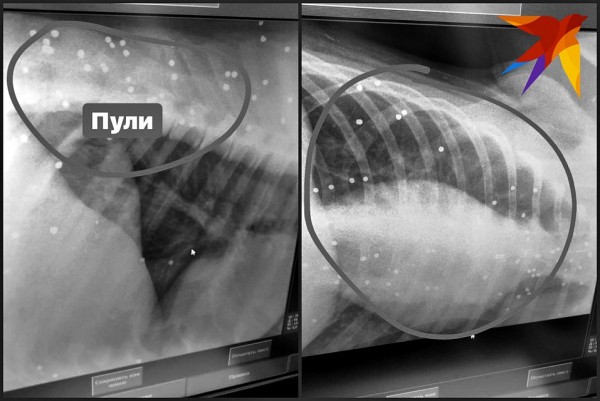

— Взяли анализы — показатели не завышены, сделала УЗИ — внутренние органы целы. Тогда решили отвезти на рентген, — продолжает Наталья Федосеева. — Тело собаки буквально изрешетили — металлическая дробь, кажется, была повсюду — в грудной клетке, в брюшной полости, в районе позвоночника. Сколько раз в нее стреляли, сказать сложно. Мы начали считать все пули, когда цифра перевалила за (!) 100, мы сбились!

Собаке сделали ренгтен и обнаружили 100 пуль Видео: instagram.com/natali_vetdoc.